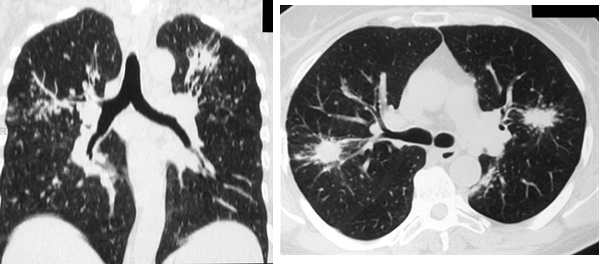

Еще одним относительно частым (20-30%) проявлением легочного саркоидоза являлся симптом локальной тени, в виде ограниченных фокусов консолидации. Как правило, изменения носили двусторонний характер с локализацией в средних и верхних легочных зонах. Контуры очагов имели преимущественно нечеткие неровные контуры, за счет инфильтрации вокруг. Нередко фокусы консолидации содержали включения воздуха. Очаги консолидации при саркоидозе отражают слияние множества мелких узелков (рис. 4, 5).

Рис. 4. РК-томограммы пациентки Г., 62 лет. Визуализируются участки альвеолярной инфильтрации округлой формы с неровными, лучистыми контурами (саркоидомы), расположенные перибронхиально

Рис. 5. РК-томограммы пациентки М., 42 лет. Субплеврально и перибронхиально с обеих сторон определяются относительно крупные очаговые тени (саркоидомы)